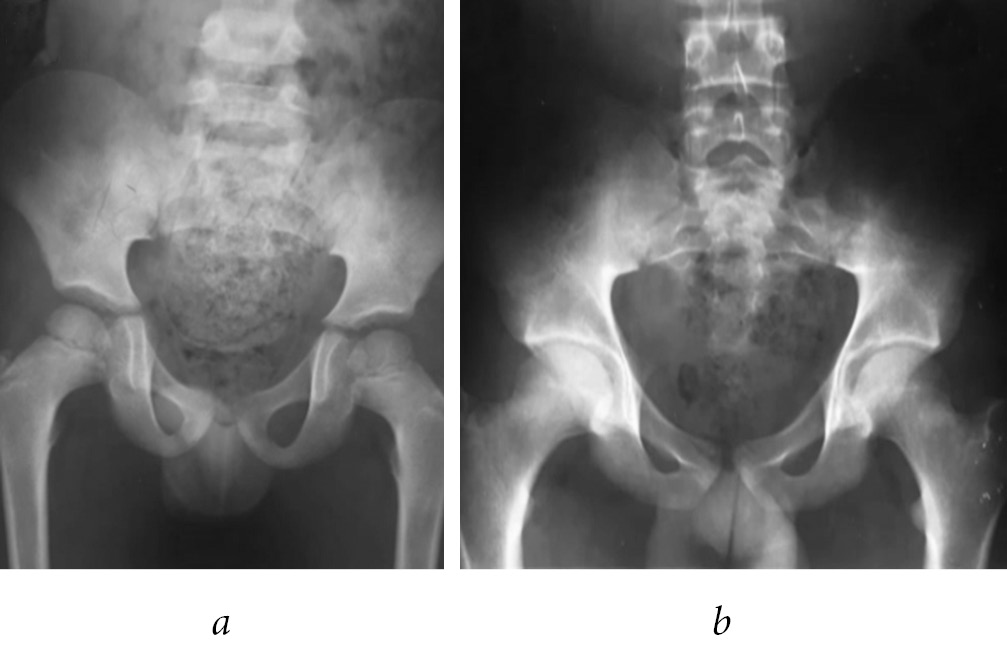

After 12 months, he was asymptomatic, without limitation of mobility arcs, performing daily activities and play without limitations (Fig. 2).

Fig. 2. Pelvis X-ray after 12 months of follow up (a); last X-ray control. Pelvis after 12 years of follow up with skeletal maturity achieved (b)

On follow-up of 12 years after the injury, at the age of 16 years-old presented independent march, without limping; full mobility arcs, a pelvic radiography was obtained and did not revealed any abnormalities.